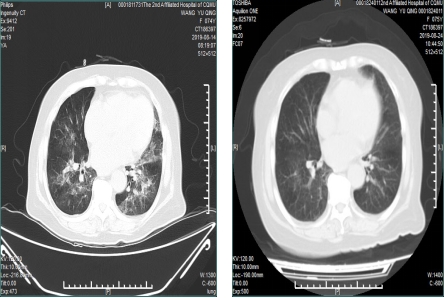

其中血肌酐:400umol/L,血管炎抗体谱:pANCA:1:10,MPO-ANCA:337RU/ml。胸部CT检查:双肺感染合并大量肺泡内出血。已经确定是非常严重的ANCA相关性血管炎累积肺、肾。经过会诊,邵阿姨被紧急转入肾内科,肾内科医生立即采取个性化治疗方案,进行积极强效治疗,重点联合双重血浆置换,给予激素联合利妥昔单抗治疗。

治疗前,患者胸部CT可见肺部感染合并严重肺泡内出血。(右图)

治疗后,患者肺部病变明显改善。(左图)